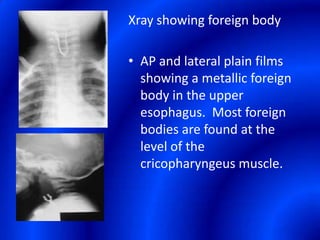

This document provides information about a barium swallow procedure. It begins with an introduction and overview of the embryology and anatomy of the pharynx and esophagus. It then describes the procedure itself, including preparation, technique, views obtained, and indications. Specific conditions that may be examined include pharyngeal and esophageal webs, foreign body impaction, scleroderma, dysphagia, mediastinal masses, and carcinoma. Diagrams are provided to illustrate normal anatomy and various pathological findings.